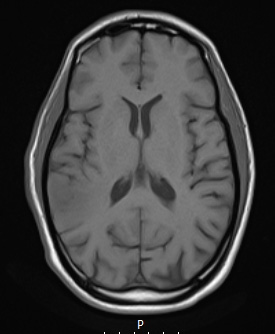

Case 12 History ---- The patient is a 37-year-old man with a history of HIV and neurosyphilis complicated by right panuveitis and blindness, who presented in September 2019 after a new-onset seizure at work. Brain MRI showed two rim-enhancing lesions in the right parietal lobe and right anterior temporal lobe, measuring 2.0 cm and 1.0 cm in greatest dimension, respectively. Operative procedure: Stealth guided brain biopsy. ---- 12A1-4 MRI studies:12A1,2 These T1-weighted images without (12A1) and with contrast (12A2) show hyperintense enhancement of a discrete mass.